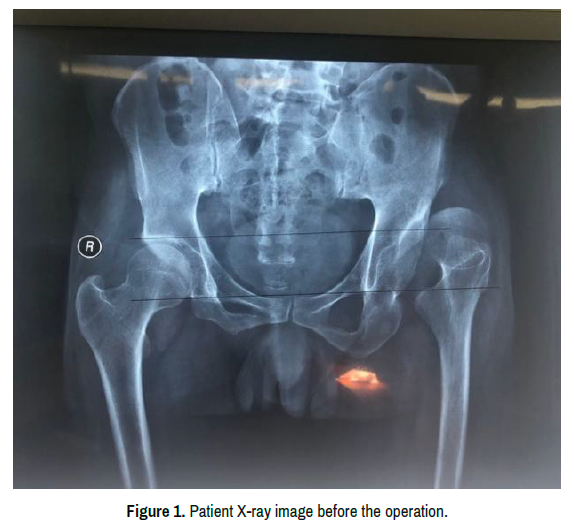

The patient we operated on is a 58-year-old male, who came to our hospital because of the limited activity of the left hip. He suffers from the intermittent pain of the hip for more than 40 years and the pain aggravated for 6 months. We X-rayed his pelvis and found that his left hip was dislocated (Figure 1). Then he was diagnosed with Crowe type IV with a Harris score of 23 and visual analogue scale (VAS) score of 8. After the physical examination, we found that the patient’s left leg is shorted by 4.2cm and he suffers from the pain of hip rotation. The degrees of right hip joint motion were as follows: adduction, 10°; internal rotation 10° and external rotation, 10°; flexion, 80° and outreach, 15°. There are no other diseases reported by the patient.

Figure 1. Patient X-ray image before the operation.